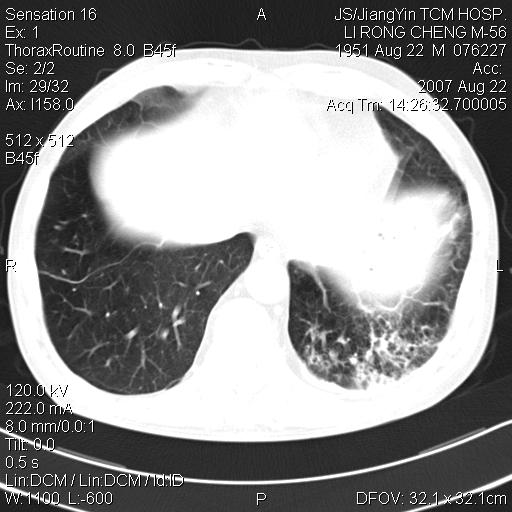

标题: CT9479:M,56Y,DM病史,咳嗽发热5天.肺脓疡.肺癌? [打印本页]

边灶边缘较光整,冠状位病灶呈大片状,,内有空洞,有胸膜反应,但无明显胸膜外侵犯征像,结合病史支持考虑肺肿脓,不排除结核,治疗后复查

好多钙化灶哦,病灶位于下叶背段,或许考虑结核更合适,做下相应检查先

周围有支气管扩张影,伴片块状高密度影,有空洞和胸膜增厚,但是肋骨未见明显破坏,考虑炎性病变可能性大。

左肺下叶见类软组织密度影,其内密度不均,有小空洞,广基与胸膜相连,其周见斑片状致密影.

考虑肺肿脓,不排除结核.

左下肺团片状类软组织密度影,形态不规则,边缘欠规整,其内可见液化区及气体影,病灶内侧见引流支气管影,相邻胸膜反应性增厚。病灶周围肺野内见增粗支气管,壁厚,边缘模糊。考虑:支气管扩张并感染;肺脓肿。